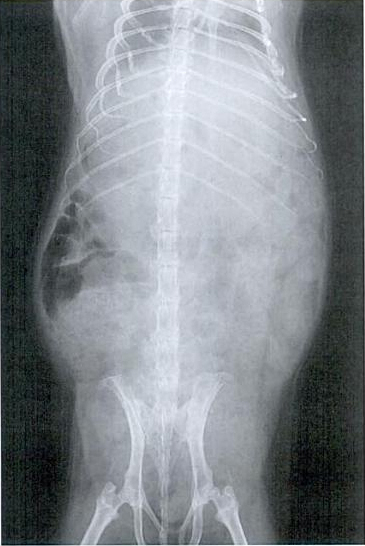

Ukoliko se plinovi ne riješe unutar par dana, potrebno je pronaći točan uzrok, pri čemu može pomoći RTG snimak.

Snimka plinovima ispunjenog abdomena: